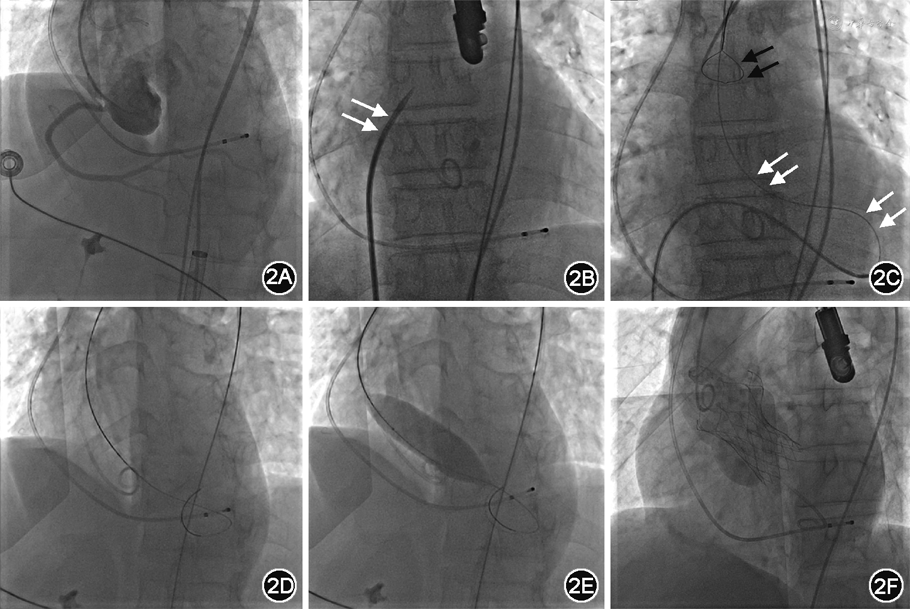

病例2 患者男,63岁,因“劳力性呼吸困难1年,加重1个月”入院。既往身体健康。入院体格检查:心律不齐,第一心音强弱不等,主动脉瓣听诊区可闻及Ⅲ/6级收缩期喷射样杂音。超声心动图示:主动脉瓣二叶式畸形(type 0型),主动脉瓣重度狭窄(瓣口面积0.5 cm2,压力阶差 84 mmHg)并轻度关闭不全,瓣膜可见重度钙化,活动受限。诊断为:重度AS。入院后经多方讨论并征求家属意见决定行TAVI治疗。手术采用全身麻醉,以右股动脉为主路,右桡动脉为辅路。术中经右股动脉在6 F Amplatzer L(美国强生公司)、JR 4.0等导管支撑下,导丝多次尝试跨主动脉瓣进入左心室,均未能成功。遂穿刺右股静脉,行房间隔穿刺。沿股静脉送260 cm超滑导丝至上腔静脉,经导丝送Swartz长鞘(美国St. Jude Medical公司),撤出导丝,经Swartz长鞘送房间隔穿刺针,前后位下拉长鞘至出现第2次跳跃,右前斜45°穿刺针弧度消失呈直线状时出针,左前斜30°造影证实穿刺针进入左心房后,沿穿刺针跟进鞘芯,退出穿刺针后经鞘芯送260 cm超滑导丝至左心房、左心室,跨主动脉瓣进入主动脉。再经右股动脉送抓捕器至降主动脉,抓捕导丝至体外完成轨道建立,最终完成手术(图2)。